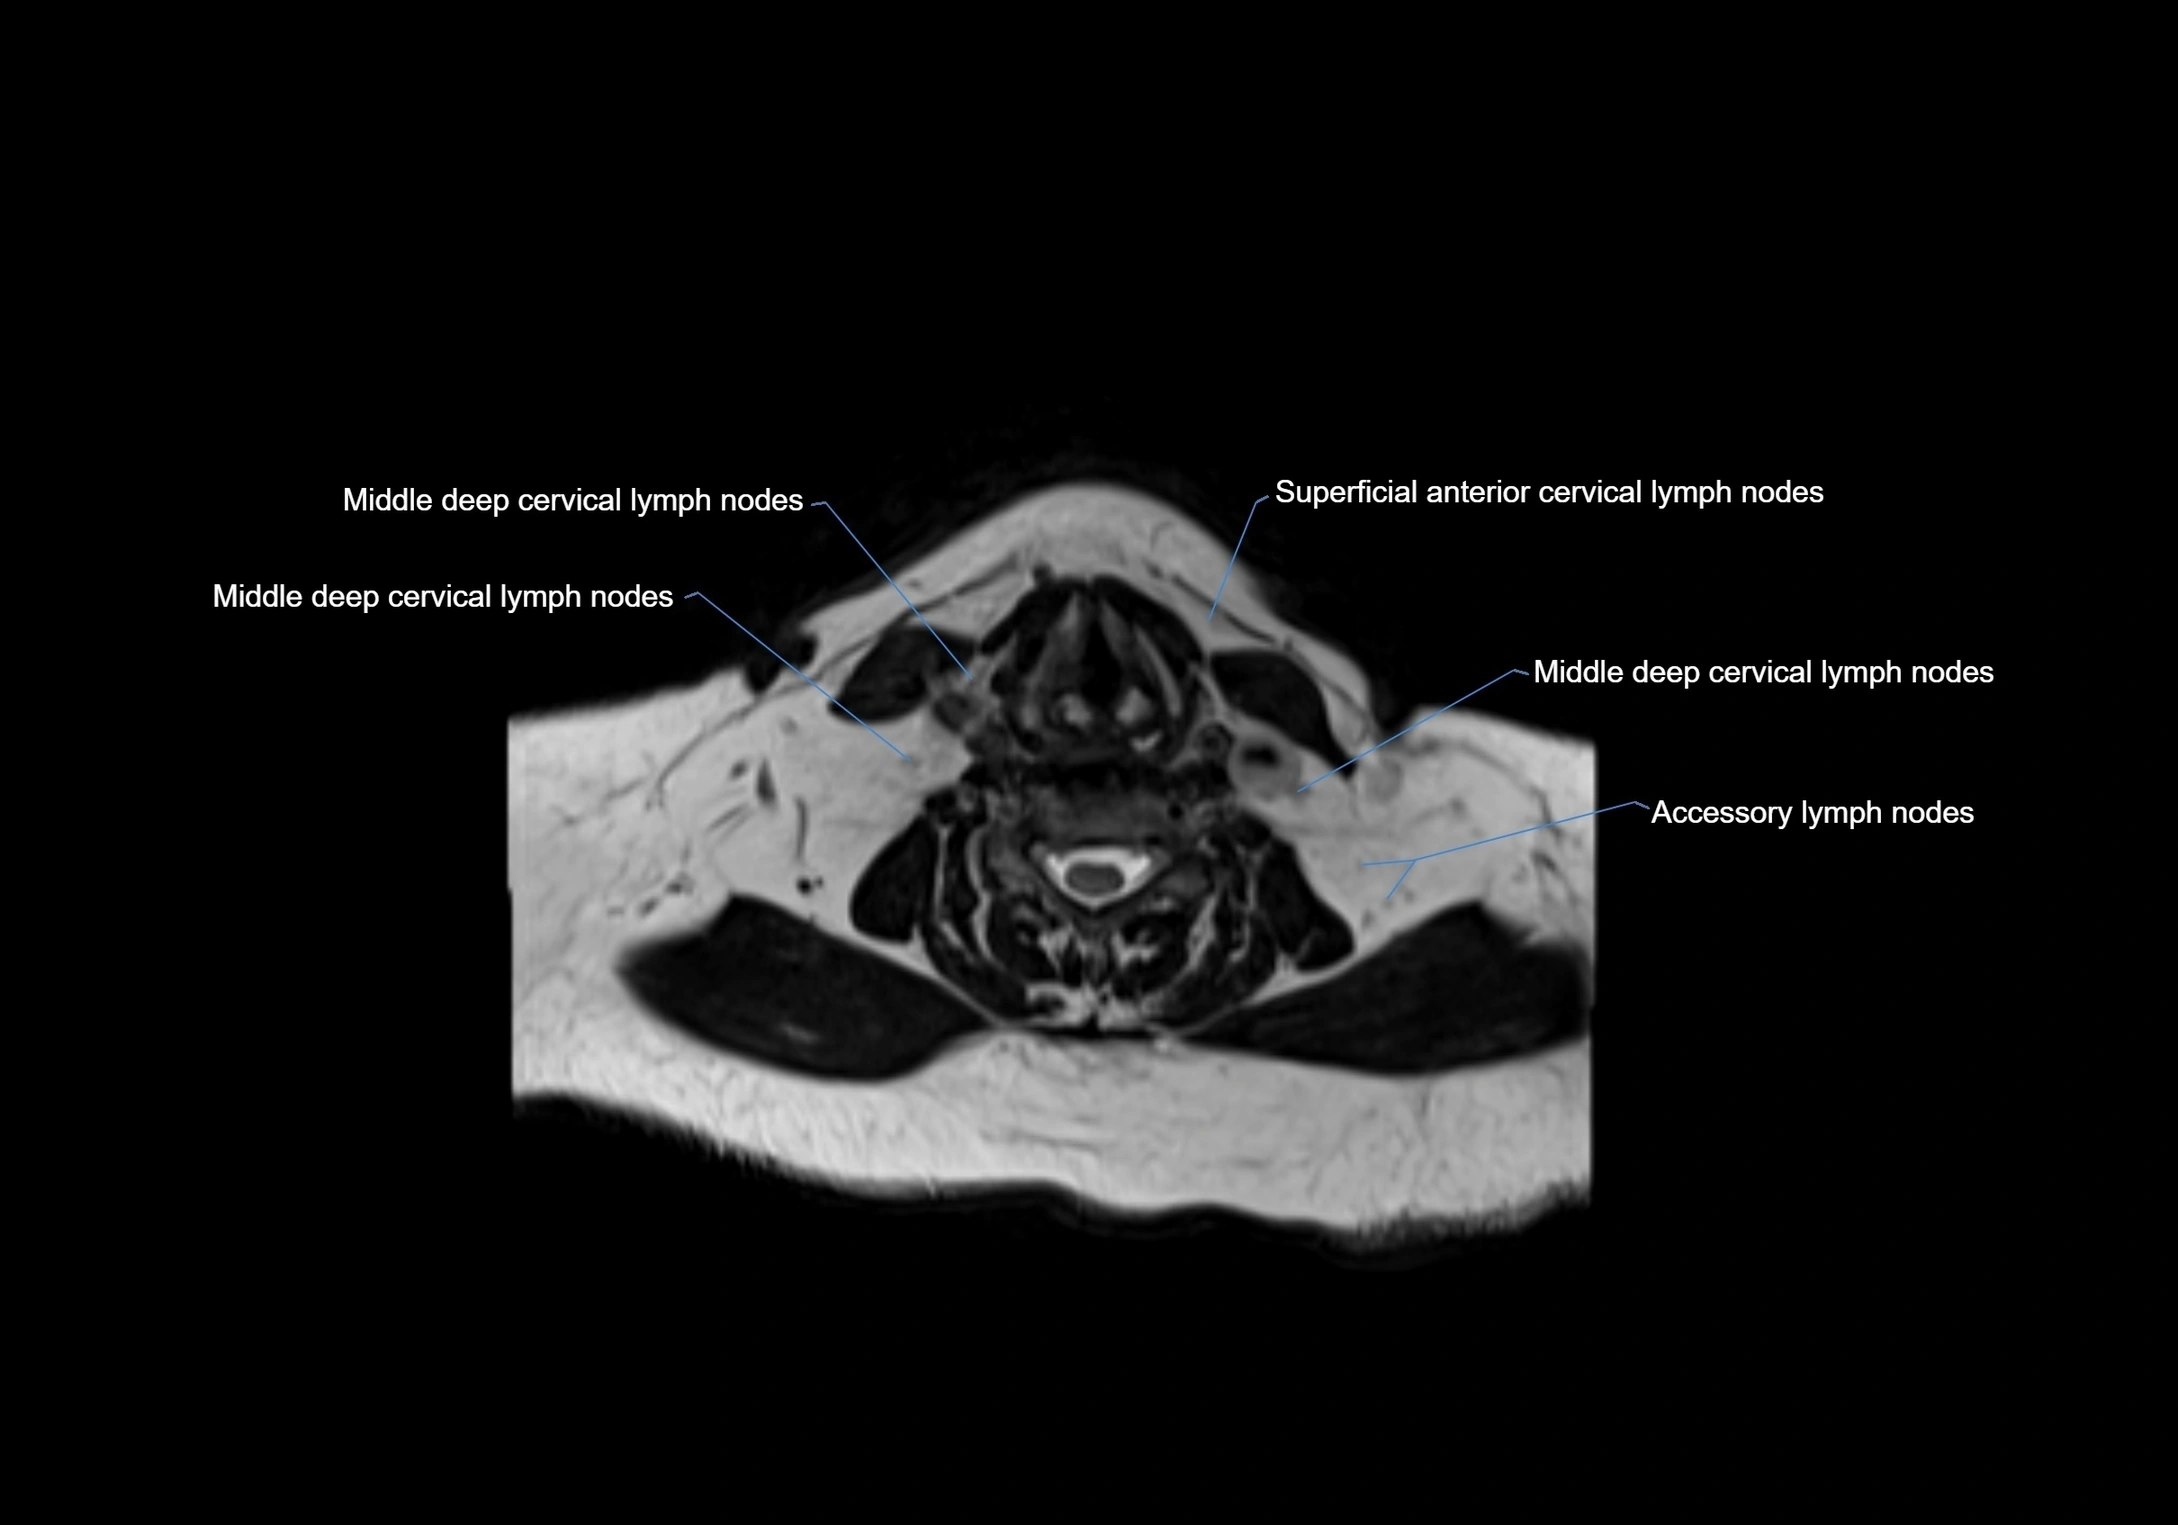

Accessory lymph nodes

Accessory lymph nodes are small, secondary lymph nodes located along the main facial and cervical lymphatic chains, often adjacent to primary lymph nodes, such as preauricular, submandibular, or occipital nodes. They are typically less than 5 mm in diameter, embedded within subcutaneous fat or connective tissue, and may be variable in number and location. These nodes provide additional filtration and immune surveillance for lymph collected from the face, scalp, and neck regions. Accessory lymph nodes are usually non-palpable in healthy individuals but may enlarge in response to infection, inflammation, or metastasis, making them clinically significant.

Location

• Found along primary lymph node chains, including preauricular, submandibular, parotid, and occipital regions

• Embedded in subcutaneous fat or superficial fascia, often lateral or posterior to primary nodes

• Variable in number; may occur unilaterally or bilaterally, depending on individual anatomy

MRI Appearance

T2-weighted images:

• Nodes show intermediate signal, with surrounding fat bright

• Useful for detecting edema, inflammation, or infiltration

• Fatty hilum may appear slightly hyperintense relative to cortex

MRI images

image